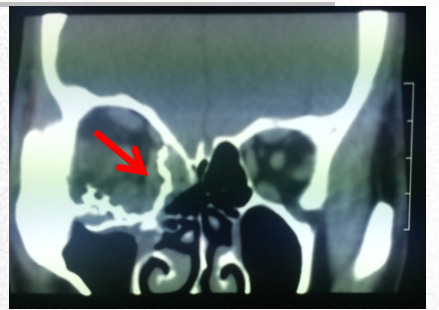

图片

图2.图中箭头所示为眶壁发生骨折